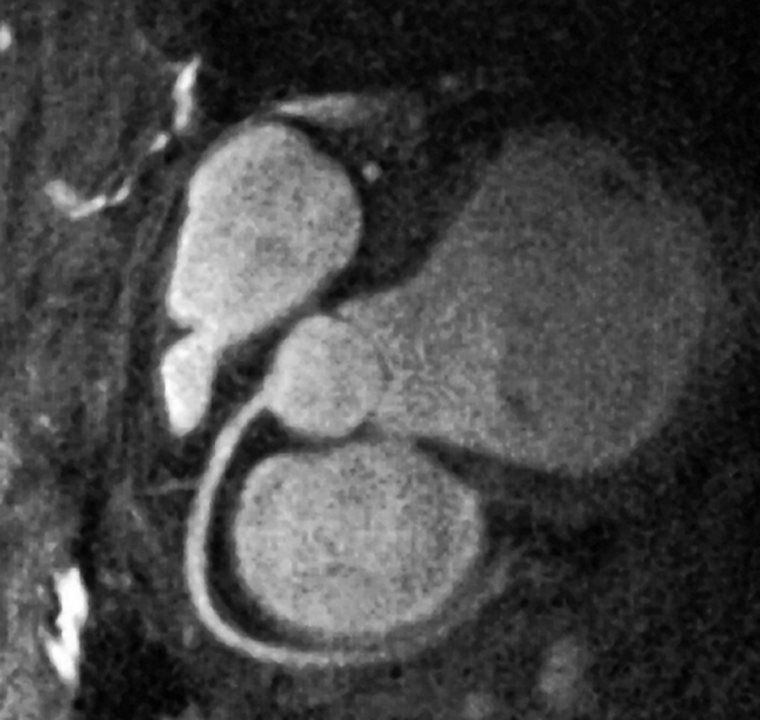

Figura 14-26:

Depiction of the coronary arteries without contrast agent application by spiral 3D ra­pid gradient-echo using navigator tech­ni­ques and diastolic gating.